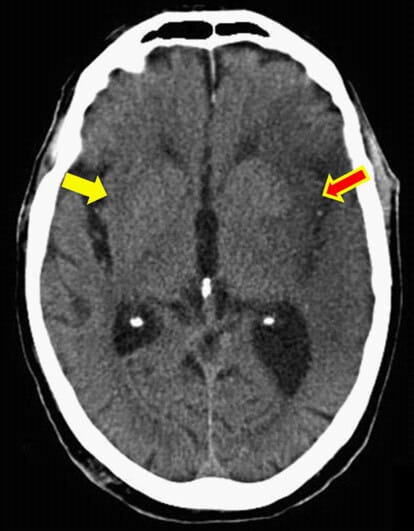

Answer: The insular ribbon sign is caused by acute middle cerebral artery (MCA) infarction. It represents the early ischemic edema affecting the insular cortex, a region supplied by the insular segment of the MCA. This ischemic insult leads to loss of the normal gray-white matter differentiation at the lateral margin of the insula, reflecting cytotoxic edema in the brain tissue. Clinically, this sign is associated with acute ischemic stroke in the MCA territory.

It is named the “insular ribbon” because the insular cortex normally appears as a thin ribbon of gray matter along the lateral margin visible on CT scans. The sign refers specifically to the loss of this distinct gray-white matter interface, hence the term โloss of the insular ribbon sign.โ

Following occlusion of the middle cerebral artery, blood flow cessation leads to ischemia and subsequent cytotoxic edema in the insular cortex. The insula lies in a vascular โwatershedโ zone most distal from collateral flow from the anterior and posterior cerebral arteries, making it highly vulnerable to ischemia. Edema causes the gray and white matter to lose their normal density contrast on CT, resulting in loss of the insular ribbon sign visibility. This early edema is one of the first radiologic signs of acute MCA territory stroke.